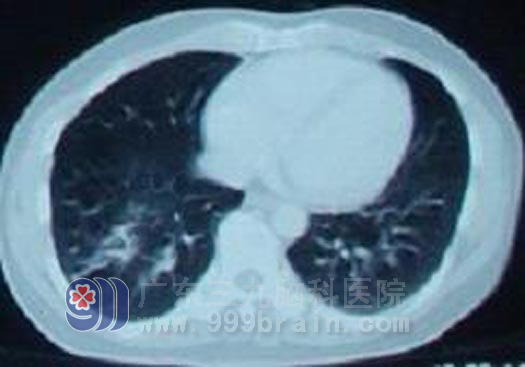

广东开平的梁先生,42岁,2010年12月开摩托车时突然晕厥,当即摔倒在地,不省人事,20分钟后意识清醒,在当地医院行头颅CT示左额顶叶多发占位。第二天即到广东三九脑科医院治疗。入院行头部MR检查示左额顶叶多发占位性病变,胸部X线示右肺下野中内带肿块影,考虑肿瘤性病变。虽然梁先生无其他躯体症状,但结合其影像检查结果考虑为肺癌脑转移。

肺部放疗前